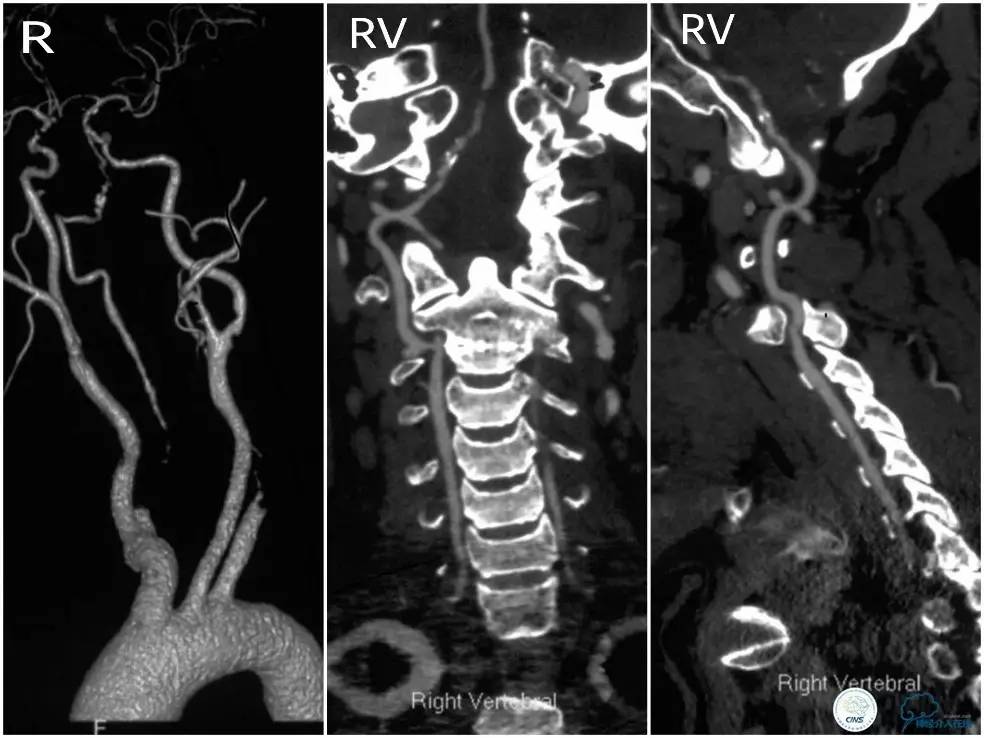

CTA:右椎动脉开口未见显影,右椎V4段钙化,右椎V4-基底动脉交界区狭窄,左椎动脉见V2段显影(图2)。

图2